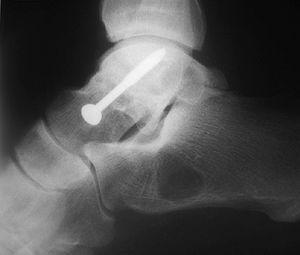

Respecto a las luxaciones del astrágalo, se han encontrado 7 casos de las cuales 5 (71,4%) de ellas eran luxaciones mediales --el pié se desplaza hacia adentro con respecto al astrágalo-- (figs. 13 y 14). La luxación medial es la más frecuentes --el 72% del total según DeLee y Curtis30 y Zimmer y Johnson31, y el 85% para Motley et al6--, seguidas de las laterales (de peor pronóstico) y mas infrecuentes las anteroposteriores.

Fig. 13. --Enucleación del astrágalo. Reducción, desbridamiento y estabilización temporal con agujas K.

Fig. 13. --Enucleation of the astragalus. Reduction, debridement and temporary stabilisation with Kirschner needles.

Fig. 14. --A) Radiografía al sexto mes: osteoporosis. B) Radiografía a los 18 meses: artrosis tibioastragalina.

Fig. 14. --a. Radiography at 6 months. b. Radiography at 18 months: tibio-astragalar arthrosis.